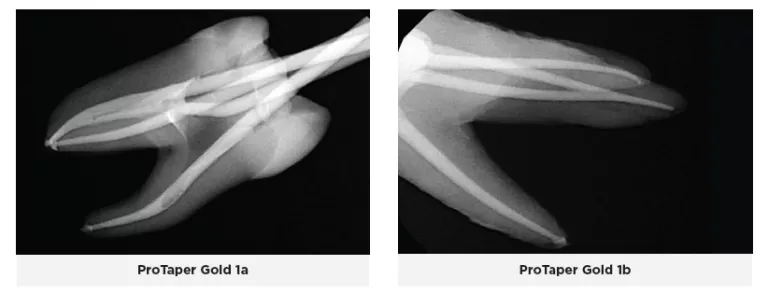

Dentsply ProTaper Gold files work by utilizing a progressive taper to sequentially preflare the coronal and middle thirds of the canal with shaping files and then separately instrument the apical third with finishing files in a stepwise fashion(13,14,15). This allows for the apical third to be instrumented without interference or engagement of the canal walls in the upper two thirds, thereby reducing the torsional stress and cyclic fatigue on the file(13,14,15). The files have non-end cutting tips, convex, triangular cross-sections with a changing helical angle and pitch over their cutting blades, and rotate on their center of mass(14). The Gold-wire technology in the ProTaper Gold files is a post-machining heat treatment process that allows for increased flexibility and strength and makes them more resistant to fracture when compared to ProTaper Universal(13).

During this trial, it was observed that the downside to this technique is that it can widen the canal too much and subsequently weaken the canal walls which may lead to root fracture, canal transportation, zipping, and perforation. This is especially true in canals with multiple multi-plane curvatures. Moreover, the flexibility decreases and file memory increases as you go up in file size above a 25 file; therefore, ledging, transporting, and straightening of the canal was noted. Because the file rotates on its own center of mass, it constantly engages the canal walls, which often results in the file being sucked in (taper lock) and can lead to binding and fracture of the file. This also lends itself to a lot of rotational force being applied to the tooth and files, especially the finishing files as they increased in size.

It was also observed that when the ProGlider glide path file was used, it made it easier to negotiate the canals and instrument them to working length and reduced the load being placed on the initial ProTaper Gold shaping files. When scouting tight and constricted canals, the Gold SX orifice opener would unwind and strip easily, as the tip is very thin and fine. This file deformation is intended to prevent the file from breaking, however if unnoticed, the file will separate.

When the canals were obturated to the corresponding Pro-Taper Gold files, the matching gutta-percha typically fit well and went to working length, with the exception of three canals where the gutta-percha extruded well out of the apex, even in situations where the file did not nor could not pass out the apex. In those situations, the gutta-percha was trimmed to fit the working length. Radiographic examination of the teeth revealed three other canals where the gutta-percha was short approximately 0.5-1mm.

Two dimensional radiographs were taken of the teeth after endodontic therapy was completed and reviewed. In some of the ProTaper Gold and Next cases, working length was not reached radiographically, even though it was thought to be achieved clinically. As an electronic apex locator cannot be used to assess working length on extracted teeth, working length was established with visual observation. Clinically, an electronic apex locator would have been used, and adjustments would have been made throughout the entire process to ensure the working length was reached. The teeth were selected at random, and some of the orifices and canals were calcified or stenotic. In a live clinical scenario, ultrasonics would have been used to negotiate these constrictions more easily; however that being said, the ZenFlex and Traverse file systems allowed these canals to be negotiated and treated without issue. Additionally, the teeth treated with the ZenFlex files appeared to have the best preservation of the natural shape of the canal and conserved the most tooth structure. This was not the case with the ProTaper Gold and Next file systems. Less efficient cutting with more aggressive removal of tooth structure was noted, resulting in a loss in the original anatomy of the canals. ZenFlex is an ideal file that balances strength and flexibility to allow clinicians to reach the working length while being minimally invasive, even in cases with complex canal anatomies.